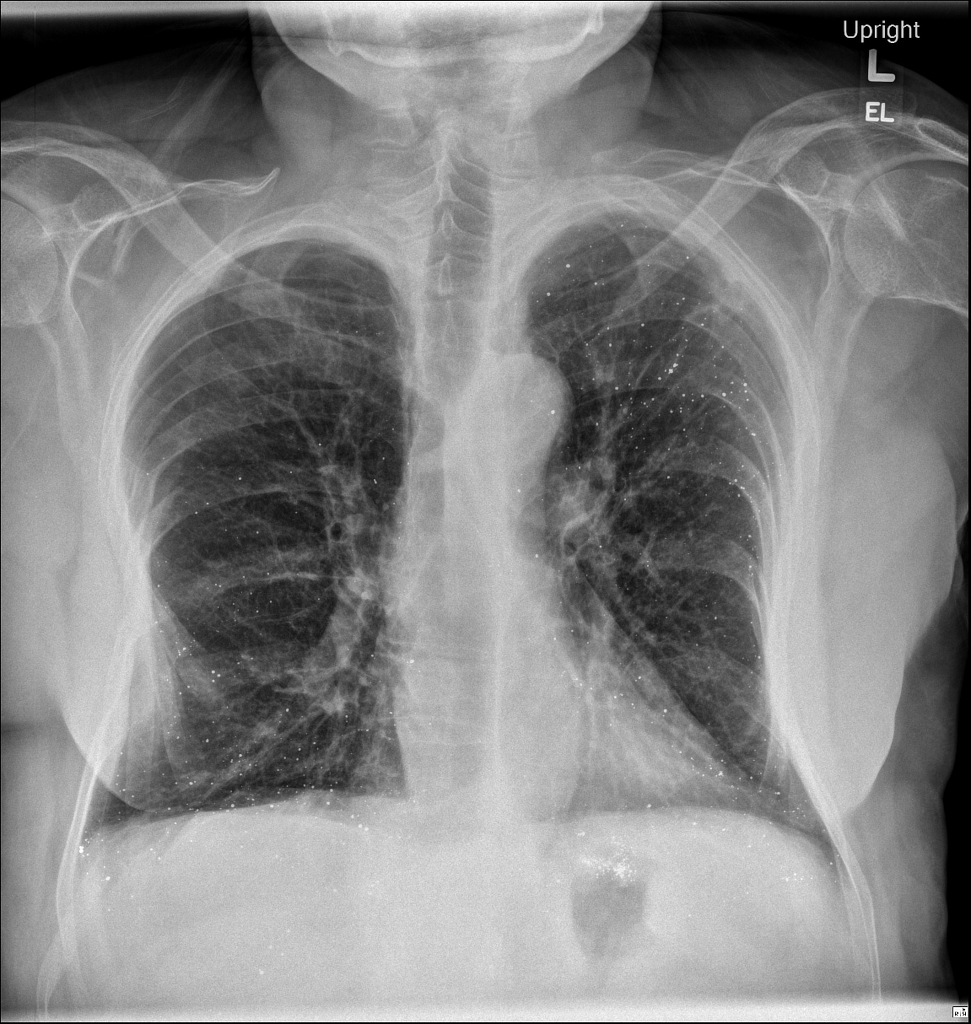

MULHER, 60 ANOS, REFERE “RESPIRAÇÃO CURTA” E TOSSE SECA HÁ VÁRIOS MESES

aumento e indefinição dos hilos pulmonares bilateralmente.

LINFADENOPATIA HILAR DEVIDO A SARCOIDOSE